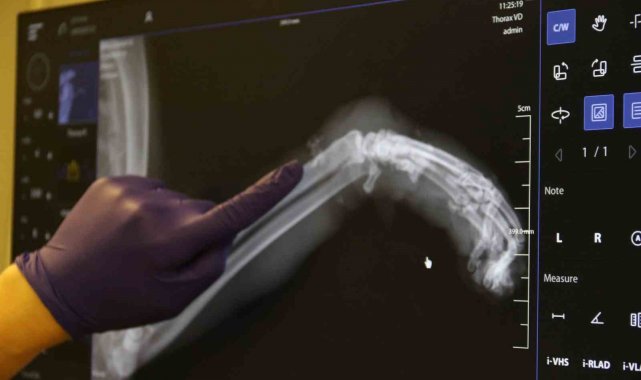

Geçtiğimiz günlerde Odunpazarı Emek Mahallesi'nde kimliği belirsiz kişi veya kişilerce bir kedinin sol ön bacağına paket lastiği takıldı. Kedinin patisine birkaç kez sıkı bir şekilde dolanan paket lastiğin talihsiz hayvanın ayağının şişmesine neden oldu. Bunu fark eden bir hayvansever kediyi Kurtuluş Mahallesi'ne bulunan bir veteriner kliniğine götürdü. Burada tedavi altına alınan hayvanın öncelikle patisindeki lastik çıkarıldı. Sol ön ayağında ödem biriken kedinin patisinin röntgeni çekildi. Antibiyotik tedavisi uygulanan kedinin ayağının kangren olma riski ve buna bağlı olarak ayağının ampute edilme ihtimali var. Tedavi altına alınan kedi gözlem altında tutuluyor.

Kedinin tedavi süreci hakkında bilgi veren Veteriner Hekim İlayda Ulus, "Kedi saat 4 gibi geldi kedimiz. Bacağı aşırı derecede şişmiş, ödenmiş şekilde geldi. Biz ilk başta kırık sandık. Ama muayene ettiğimizde 4-5 kere bağlanacak şekilde lastiğin burasını boğmuş olduğunu gördük. Bu bilinçli şekilde yapılmış. Dolaşım bozmak adına. Kimin yaptığını bilmiyoruz. Hasta sahibimiz getirdi çok üzülerek. Biz de tedaviye başladık şu anlık. Sokak kedisi, birisi sadece dükkanında bakıyormuş, gidip geliyormuş. Bir haftadır yokmuş kedisi. Aramışlar, birisi haber vermiş tasmasından bularak o şekilde geldi. Oradaki tüyleri özellikle tıraş ettik. Ölü dokuları aldık. Baya bir kan toplamış ve ölü dokular birikmiş. Onları temizledik, tıraş ettik. Antibiyotik tedavisine başladık. Şu anda sabah akşam olacak şekilde krem sürüyoruz. Yarın tedavisi yapıyoruz. Oradaki kan akımını hızlandıracak kremler, özellikle fizik tedaviler uyguluyoruz. Şu anda 3-4 gün takip edeceğiz. Eğer iyileşme görmezsek amputeye doğru gidebiliriz. Şu anda sol ön ayağını kaybetme ihtimali var. Birkaç kere böyle tasma boğulmuş şekilde geldi, boyundan yara almış kediler. Başka tekme çok geldi, göğüs kırıkları. Bu tür vakaları gördük. Onların ağzı var, dili yok. Bizden daha daha masumlar. Bu şekilde olması bizi çok üzüyor, derinden üzüyor. Hayvan sevmeyen, insan sevemez. Bu şekilde çok daha duyarlı ve dikkatli olmalarını bekliyoruz" dedi.